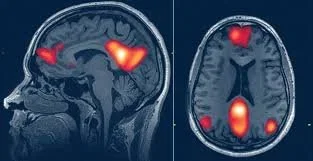

One of the most significant physiological changes during hypnosis is the alteration in brain activity patterns. Functional magnetic resonance imaging (fMRI) and electroencephalography (EEG) are commonly used to study these changes:

• Decreased Activity in the Dorsal Anterior Cingulate Cortex (dACC): Studies have shown that during hypnosis, there is a notable decrease in activity within the dACC, which is associated with monitoring and evaluating external stimuli. This reduction suggests that individuals become less aware of their surroundings and more absorbed in internal experiences[1].

• Increased Connectivity Between Brain Regions: Research indicates enhanced connectivity between the dorsolateral prefrontal cortex (DLPFC) and the insula during hypnosis. This connection is thought to facilitate better integration of bodily sensations and cognitive processes, allowing for improved control over physical responses[2].

• Theta Wave Activity: Hypnosis is associated with increased theta wave activity in the brain. Theta waves are linked to states of relaxation and creativity, suggesting that individuals may experience altered states of consciousness during hypnosis[3].

3.1 Neuroimaging Techniques

Recent advancements in neuroimaging have allowed researchers to explore the physiological correlates of hypnotic states more thoroughly. Functional Magnetic Resonance Imaging (fMRI) studies have shown distinct patterns of brain activity associated with different depths of hypnosis (Oakley & Halligan, "Hypnosis and Suggestion," Nature Reviews Neuroscience). These imaging techniques provide objective data regarding changes in brain function that correlate with subjective reports from participants.

Electroencephalography (EEG) is another method used to assess depth by measuring electrical activity in the brain during hypnosis sessions. Studies have indicated that certain EEG patterns—such as increased theta wave activity—are associated with deeper states of hypnosis (Tart, States of Consciousness). This method allows for real-time monitoring and provides quantitative data regarding alterations in consciousness.